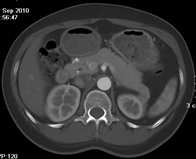

如上圖所示,相鄰的三張軸位圖像未見(jiàn)明顯異常,根據(jù)傳統(tǒng)軸位圖像很難得到準(zhǔn)確的臨床診斷。

同一病人利用容積數(shù)據(jù)進(jìn)行三維處理后,高品質(zhì)MPR和三維圖像上則清晰顯示了縱向排列的腹腔干與腸系膜上動(dòng)脈相鄰近,血管發(fā)生變 異,近端血管閉塞,為臨床提供了精確的診斷信息。